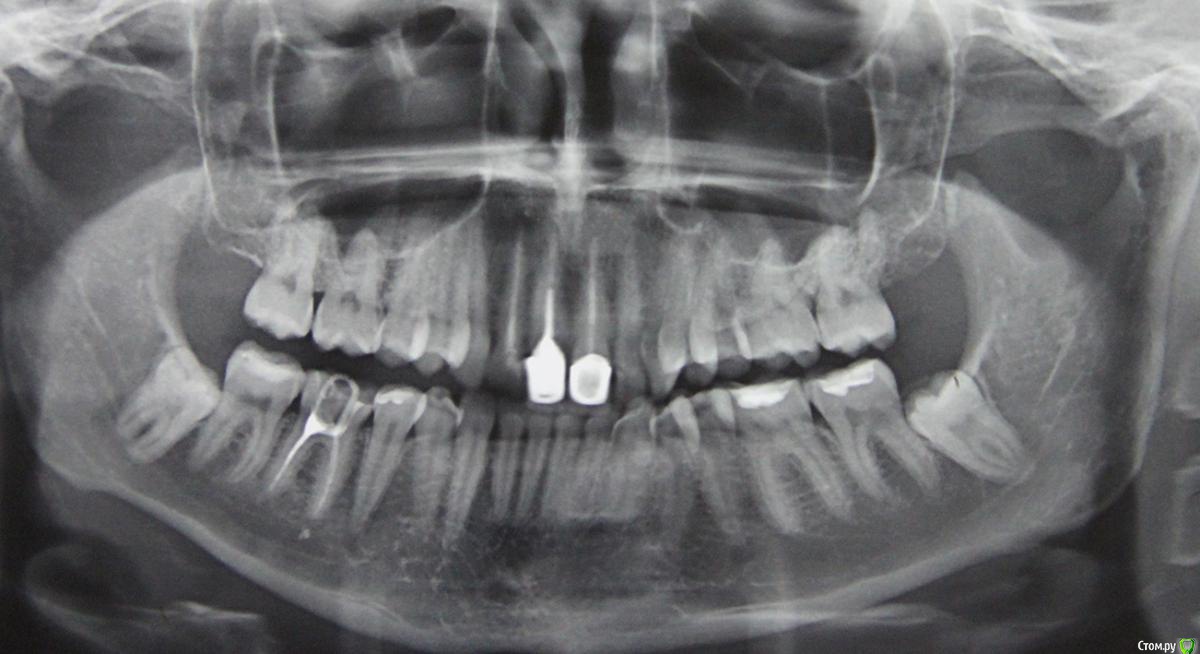

luma Опубликовано 10 апреля, 2016 Поделиться Опубликовано 10 апреля, 2016 Доброго времени суток!2,5 года назад сломался передний зуб (оба передних верхних зуба были давно пролечены, каналы запломбированы).Пошла по рекомендации к знакомому знакомых стоматологу..Итог: мне сказали, что раз один зуб сломался, значит и второй в любой момент может сломаться также, поэтому надо делать коронки сразу на оба зуба. Сделали, металокерамика. Правая коронка несколько раз вываливалась, ездила повторно, ее снова вставляли. Вроде сидит хорошо. Но беда с левой коронкой: во-первых, там щель с обратной стороны, зазор такой, можно язык порезать об край коронки. Во-вторых, на левой коронке образовался карман с передней стороны, там скапливается еда, гноится постоянно. Я обращалась к нескольким врачам с этим вопросом. Ответом было - либо полоскать, ждать когда само пройдет.. Либо страшные рассказы о том, как сложно спиливать коронку, вынимать вкладку и заново все делать... Время идет, карман не зарастает, я каждый день несколько раз этот гной удаляю ватной палочкой. Мне 30 лет. Хочется сделать и красиво, и надежно.. чтоб не бояться улыбаться больше.Может быть, кто-то знает, кто возьмется переделать эту коронку? Или как можно это вылечить? Куда обращаться?Спасибо.Москва. Ссылка на комментарий

luma Опубликовано 11 апреля, 2016 Автор Поделиться Опубликовано 11 апреля, 2016 можете сделать фото?Вот фото прикладываю. Синим пунктиром выделила зону, откуда гной (или что там еще бело-зеленое может быть) удаляю. Ссылка на комментарий

IvanK Опубликовано 12 апреля, 2016 Поделиться Опубликовано 12 апреля, 2016 нужно сходить на очную консультацию к ортопеду, посмотреть уровень уступа коронок, прилигание, дальше решать вместе с ортодонтом, ортопедом, хирургом в общем без очной консультации не обойтись Ссылка на комментарий